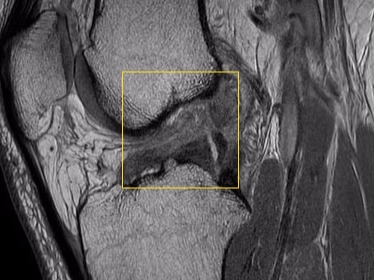

Diagnostik

Diagnose durch Ultraschall, inkl. Nachbefundung von Röntgen, Ultraschall, MRT und CT

Meniscustransplantation

State of the Art